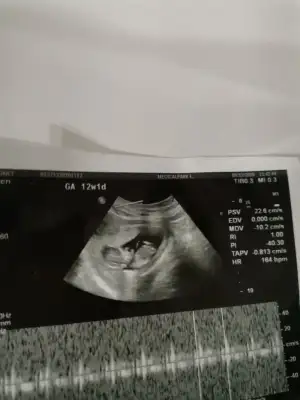

dr soylemeden siz gorun genital nub teorisi ( bebegin cinsiyeti)

yaa cok bekledım seni carsambadan berı mesajım cok arkada kaldı bana da lutfen yorumm 11+1 dim ama ultrason da 12 cıktım